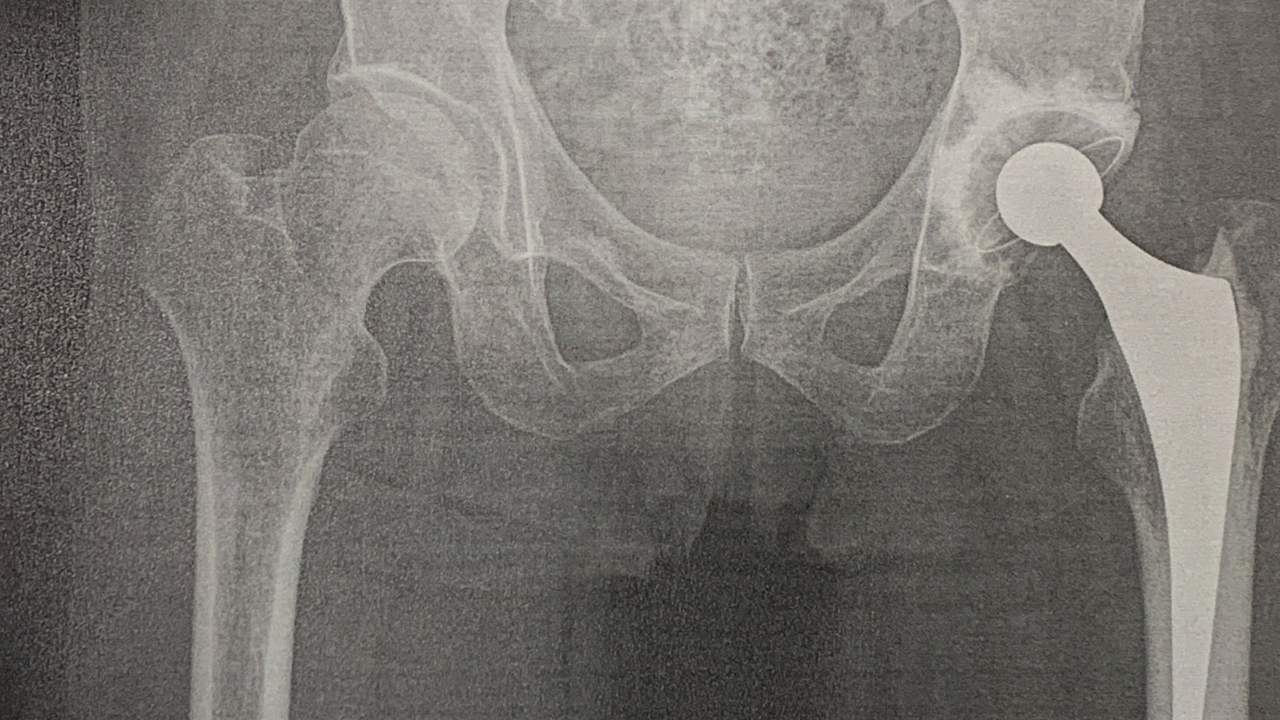

まずはレントゲン撮影で

その後に診察です。

股関節 レントゲン画像.png

レントゲン結果も問題無く

患部の触診等でも問題無く

次回の診察は来年の春頃。

人工関節の寿命が

普通に使えば 25年程度

経年劣化と

使用頻度での消耗も有り

交換手術が必要で、

その時期に再診が必要になります。